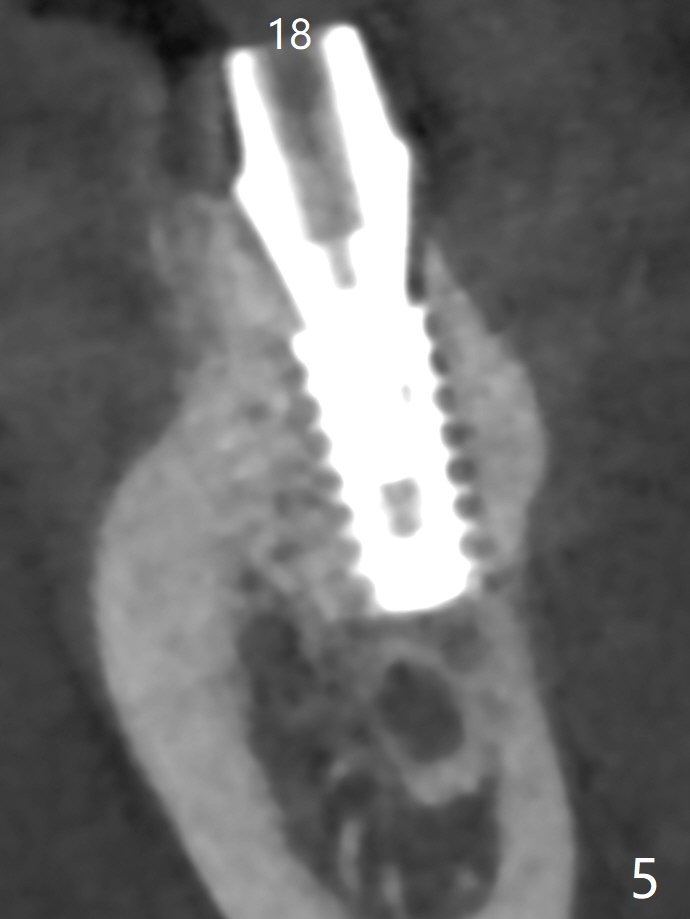

The female woman is afraid of pain. After placement of 4x9 mm FC implant at #19, infiltration anesthesia is not enough for osteotomy at #18. Block anesthesia is added. When a 5x9 mm FC implant is placed in the osteotomy (designed for 5x8.5 mm IS one), it is close to the Inferior Alveolar Canal (Fig.1 red dashed line; Fig.2 (*: bone graft with PRF)). The third contributing factor is the pressure upon the distal end of the distal end guide while osteotomy. A few hours later, the patient reports no paresthesia. The implant placement level and trajectory are normal at #18 and 19 (Fig.3-5). To check pair abutment seating with 30 Ncm torque, PA is taken after removal of healing abutments 4 months postop (Fig.6-8). First the cuff of the abutment is short, subgingival distal of #18 (Fig.6 * (gingiva)). When an abutment with longer cuff is placed, it appears to be close to the distal crestal bone (Fig.7 *). Finally a smaller abutment seams to be appropriate (Fig.8). Retrospectively the larger abutment (6.5x4(4) mm) is incompletely seated initially (Fig.1 with gap).